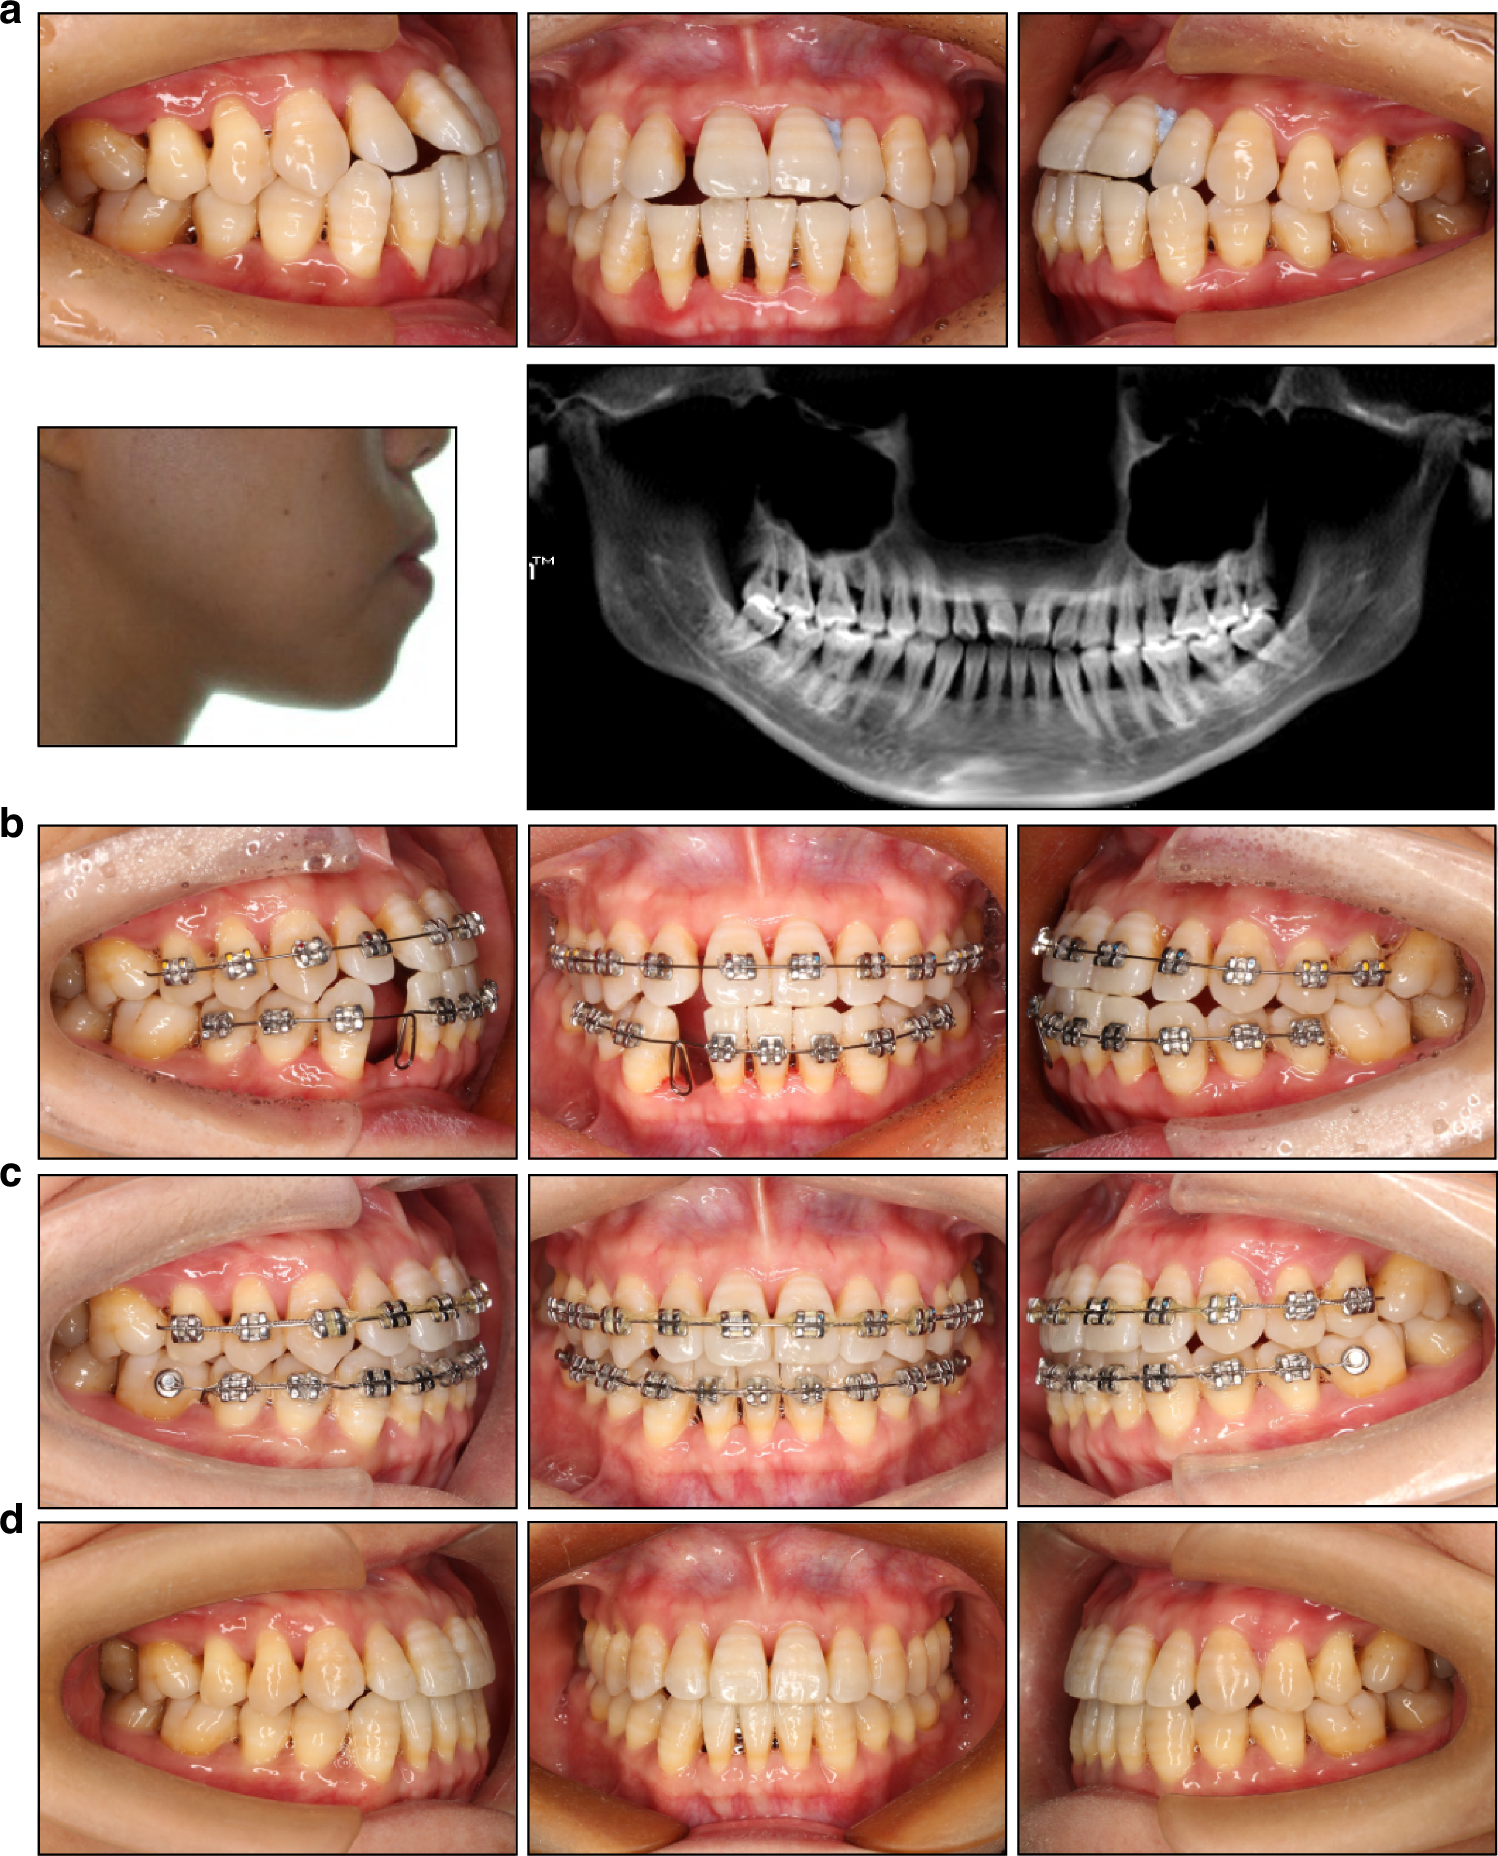

Fig. 5

Treatment of a 34-year-old periodontally compromised female patient. a Pretreatment intraoral view, facial profile, and panoramic radiograph. The edge-to-edge bite, a full unit Class III molar relationship on the left side, and severe bone loss are evident. b The treatment goal is to eliminate occlusal trauma and improve occlusal contact, without excessively emphasizing on correcting the facial profile or molar relationships. Therefore, tooth 42, with the poorest periodontal condition, was selected for extraction. The first molars were strategically left unbonded to preserve their position and facilitate oral hygiene. c Lingual buttons were bonded on the mandibular first molars to close residual spaces. d Posttreatment intraoral view